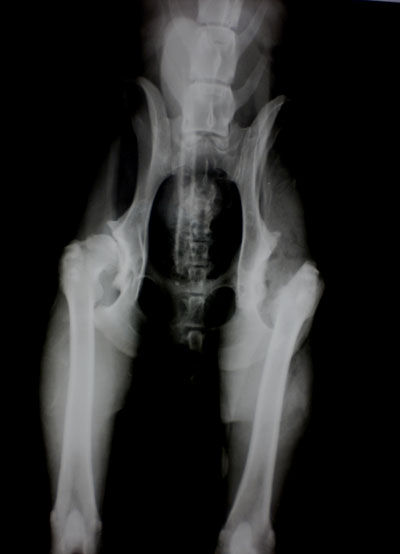

Укладка пациента при проведении рентгенографии на дисплазию ТБС

Рентгенография является основным методом диагностики дисплазии тазобедренных суставов.

При проведении рентгенологического исследования животное располагается на спине с вытянутыми тазовыми конечностями. На рентгенограмме в зависимости от степени дисплазии (А, B, C, D, E) определяются различные рентгенологические признаки. Впервые рентгенологическая оценка ДТБС была дана в 1966 году Ортопедическим фондом животных образованным John Olin.

Рентген ТБС собаки. Норма

Рентген ТБС собаки. Двусторонняя дисплазия, артроз